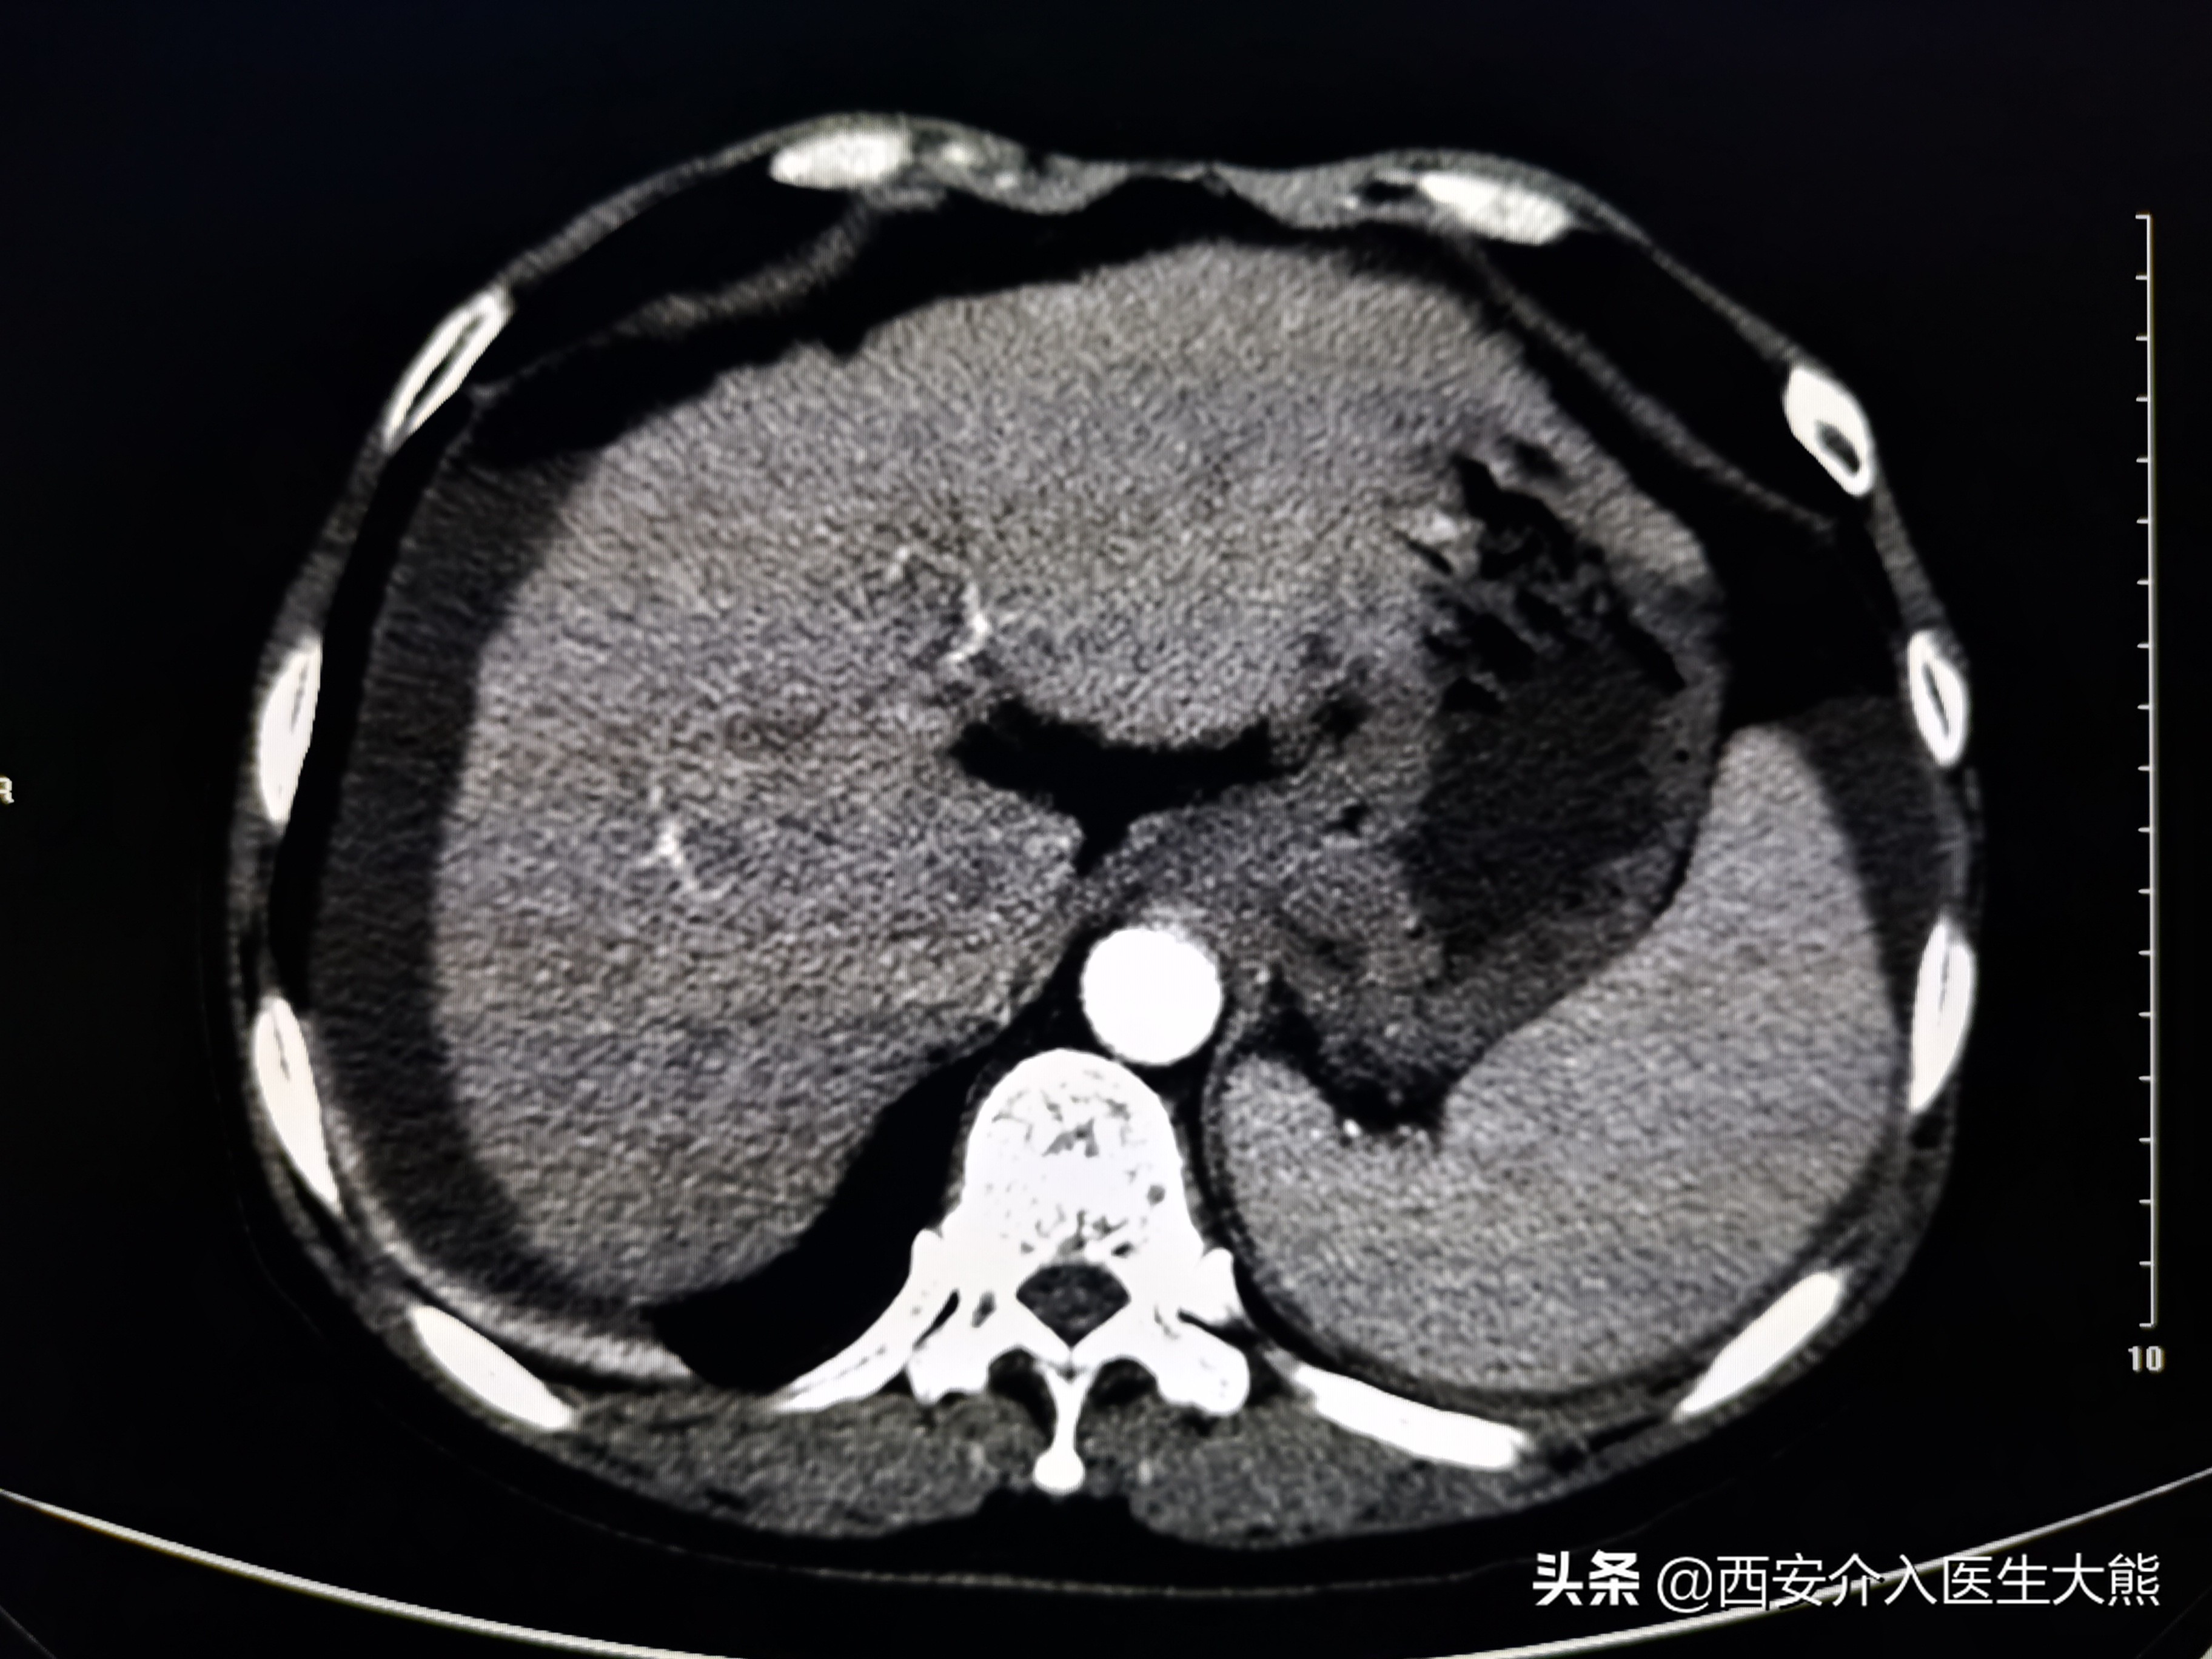

1、CT(2021-11-8):(1)、肝硬化(脾大、门静脉高压、食管胃底静脉曲张,门静脉高压。胆汁淤积,胆囊壁水肿性改变;左肾萎缩,左肾盏结石;(4)、膀胱导尿术后改变;子宫显示不清;直肠CT平扫未见异常。

缩小硬化的肝脏

扩张的脾静脉

扩张的胃底静脉

这名患者的治疗过程就符合该治疗策略。术前的CT平扫已经显示极度扩张的胃冠状静脉,这在DSA影像上得到证实。2018年患者第二次出血时做的增强CT上已经显示出患者的胃冠状静脉扩张。此时,已经具有行TIPS的指征。在经过3年的变化后,病情是急剧加重。如果出血剧烈、生命体征不平稳,或各种原因导致不能行急诊胃镜的情况下,不要错过TIPS降低门脉压力的机会。

胃镜和增强CT是评估患者病情的重要措施。该患者由于病情严重,每一次搬动,都增加了患者再次出血的风险,所以未能完善这2项检查。但是CT平扫的结果证实门静脉及属支的扩张,在某种程度上替代了胃镜的作用。但是不能忽视的是,仍有部分患者可能是消化道溃疡导致出血。根据目前指南的推荐,在病情允许的情况下,应该尽早完善胃镜检查和增强CT。如果病情不允许,普通CT平扫亦能提供部分诊疗信息。